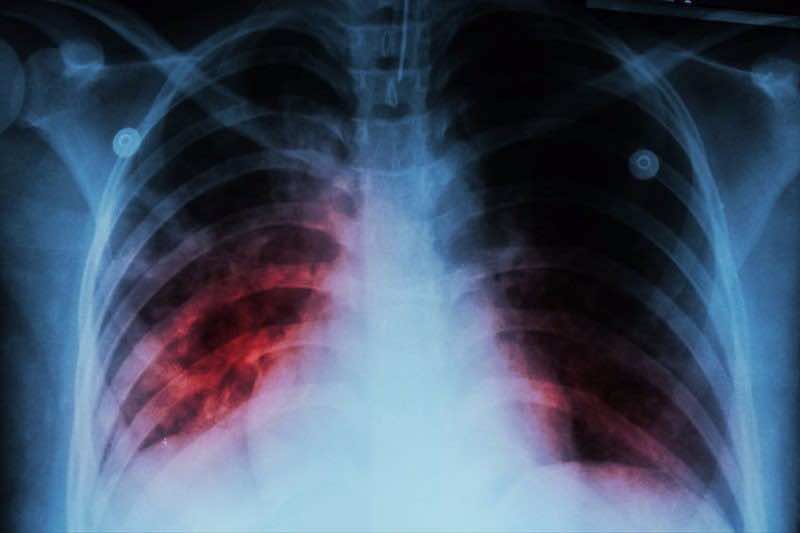

Morocco’s Ministry of Health and Social Protection has revealed that 53% of new tuberculosis (TB) cases recorded in 2025 involve forms of the disease that affect parts of the body outside the lungs. The post Over Half of New Tuberculosis Cases in Morocco Affect Organs Beyond Lungs appeared first on Morocco World News .